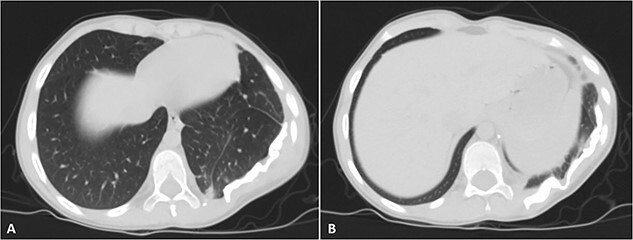

Figure 2.

Selected axial CT images with mediastinal windowing showing multiple cuts of the patient’s chest. A huge relatively well-defined heterogeneous mass lesion is noted occupying the left lower hemi-thorax causing left lung volume loss and significant rightward mediastinal shift. No definite invasion of the adjacent ribs, however, remodeling of the lower aspect of the left posterior tenth rib is noted with the widening of the left tenth intercostal space and involvement of the left erector spinae muscles by the previously mentioned mass.